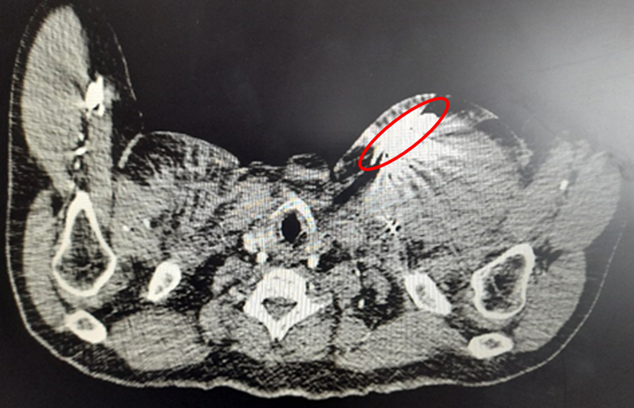

ETE al ingreso.TC craneo que evidencia HIC.

Sin embargo, 48 horas después de suspender la fibrinólisis e iniciar anticoagulación con heparina y warfarina, la paciente desarrolló cefalea intensa, diagnosticándose HIC. Se suspendió la anticoagulación y se adoptó una conducta expectante en conjunto con neurocirugía. Tras siete días con buena evolución clínica, tomografica y ecocardiográfica, y considerando la evidencia disponible y balance riesgo/beneficio, se decidió reintroducir anticoagulación con heparina no fraccionada bajo monitoreo estricto. Se destaca que no hubo agravamiento de la HIC. Las semanas posteriores, en la transición a warfarina se comprobó nueva trombosis protésica por aumento de gradientes decidiéndose realizar cirugía de sustitución de la prótesis mecánica mitral por una bioprótesis. La paciente evolucionó favorablemente tras la cirugía, sin complicaciones perioperatorias, quedando anticoagulada con enoxaparina por 3 meses.